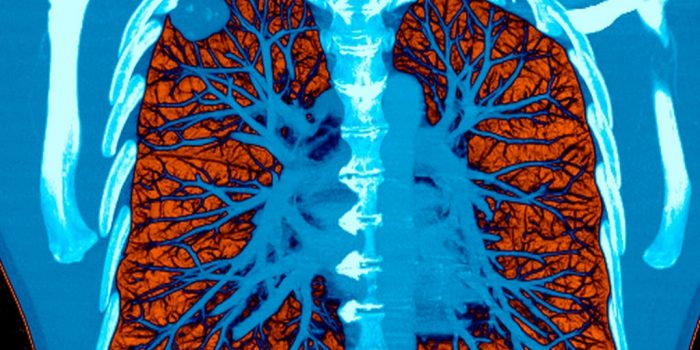

当技术与医学结合时,会产生神奇的拯救生命的效果,这是医学突破的最终目标。人工智能(AI)的新技术已经出现了早期迹象肺癌检测.科学家们表示,这种方法可以比常规的癌症检测方法提前一年检测出癌症。

这一突破是由这项新研究在欧洲呼吸学会国际大会上发表.肺癌已成为导致肺癌患者死亡的最常见原因。它每年在全球夺走大约180万人的生命。然而,肺癌在体内的检测往往是在癌症阶段很长一段时间才被观察到。这意味着,即使被发现,它也处于无法治疗或治愈的阶段。

这就是人工智能(AI)带来这种方法的原因。传统的计算机断层扫描(CT)已经可以揭示肺部肿瘤的特征,CT后的活检或手术可以确认肿瘤的恶性。但每次扫描都需要一位放射科专家,他必须查看大约300张肺部肿瘤的关键迹象,这些迹象可能非常微妙,很容易被忽略,而且非常微小。

该人工智能程序通过对888名已经接受常规测试的患者的CT扫描进行训练。这项技术在1179名患者身上进行了测试。在一组已确诊的177名患者中,有172人被正确检测出患有癌症。这使得AI的准确率达到了97%,这是非常令人印象深刻的。这个程序只帮助放射科医生吗而不是取代他们。